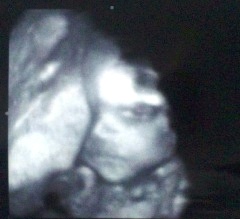

逆子だと初めて言われた写真。

逆子の為か顔がアップ!思わず『コワッ』と言ってしまった心霊写真のような我が子(笑)